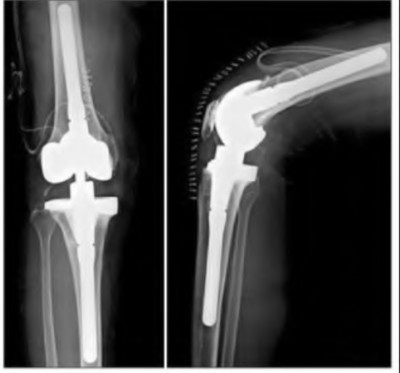

During a revision total knee arthroplasty, removal of the tibial component reveals a massive contained metaphyseal defect measuring 3 cm deep, but with an intact cortical rim. According to the Anderson Orthopaedic Research Institute (AORI) classification, what type of defect is this, and what is the preferred method of management?

In revision TKA for severe AORI Type 2b or 3 metaphyseal bone defects, highly porous metaphyseal titanium cones are increasingly utilized. What is their primary biomechanical and biologic advantage over standard structural allografts?